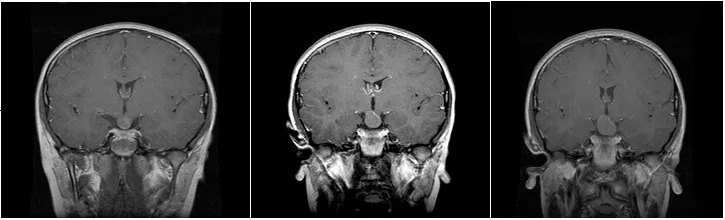

在顱咽管瘤術(shù)前考慮中,需要著重考量腫瘤的主要位置(交叉前、鞍后、交叉后),以及腫瘤與交叉、下丘腦附著的關(guān)系,垂體漏斗和垂體柄的位置,大而復(fù)雜的腫瘤可能需要聯(lián)合不同入路手術(shù)。

顱咽管瘤手術(shù)首要目標(biāo)是安全、徹底地到達(dá)并切除腫瘤;其次,要盡可能保留垂體柄。之所以要重點(diǎn)保護(hù)這兩者,是因?yàn)樗鼈儗?duì)于患兒未來的生活質(zhì)量極為重要。垂體柄涉及激素的分泌,下丘腦則像汽車的剎車和油門,負(fù)責(zé)調(diào)控激素分泌的節(jié)奏。

除此之外,手術(shù)還必須在不損傷視神經(jīng)等關(guān)鍵結(jié)構(gòu)的前提下,盡量實(shí)現(xiàn)腫瘤的全切除,防止復(fù)發(fā)。對(duì)于顱咽管瘤手術(shù)來說,保護(hù)垂體柄和視神經(jīng)功能的完整是主要的,如果能在這一前提下實(shí)現(xiàn)完全切除,則達(dá)到了理想的效果。